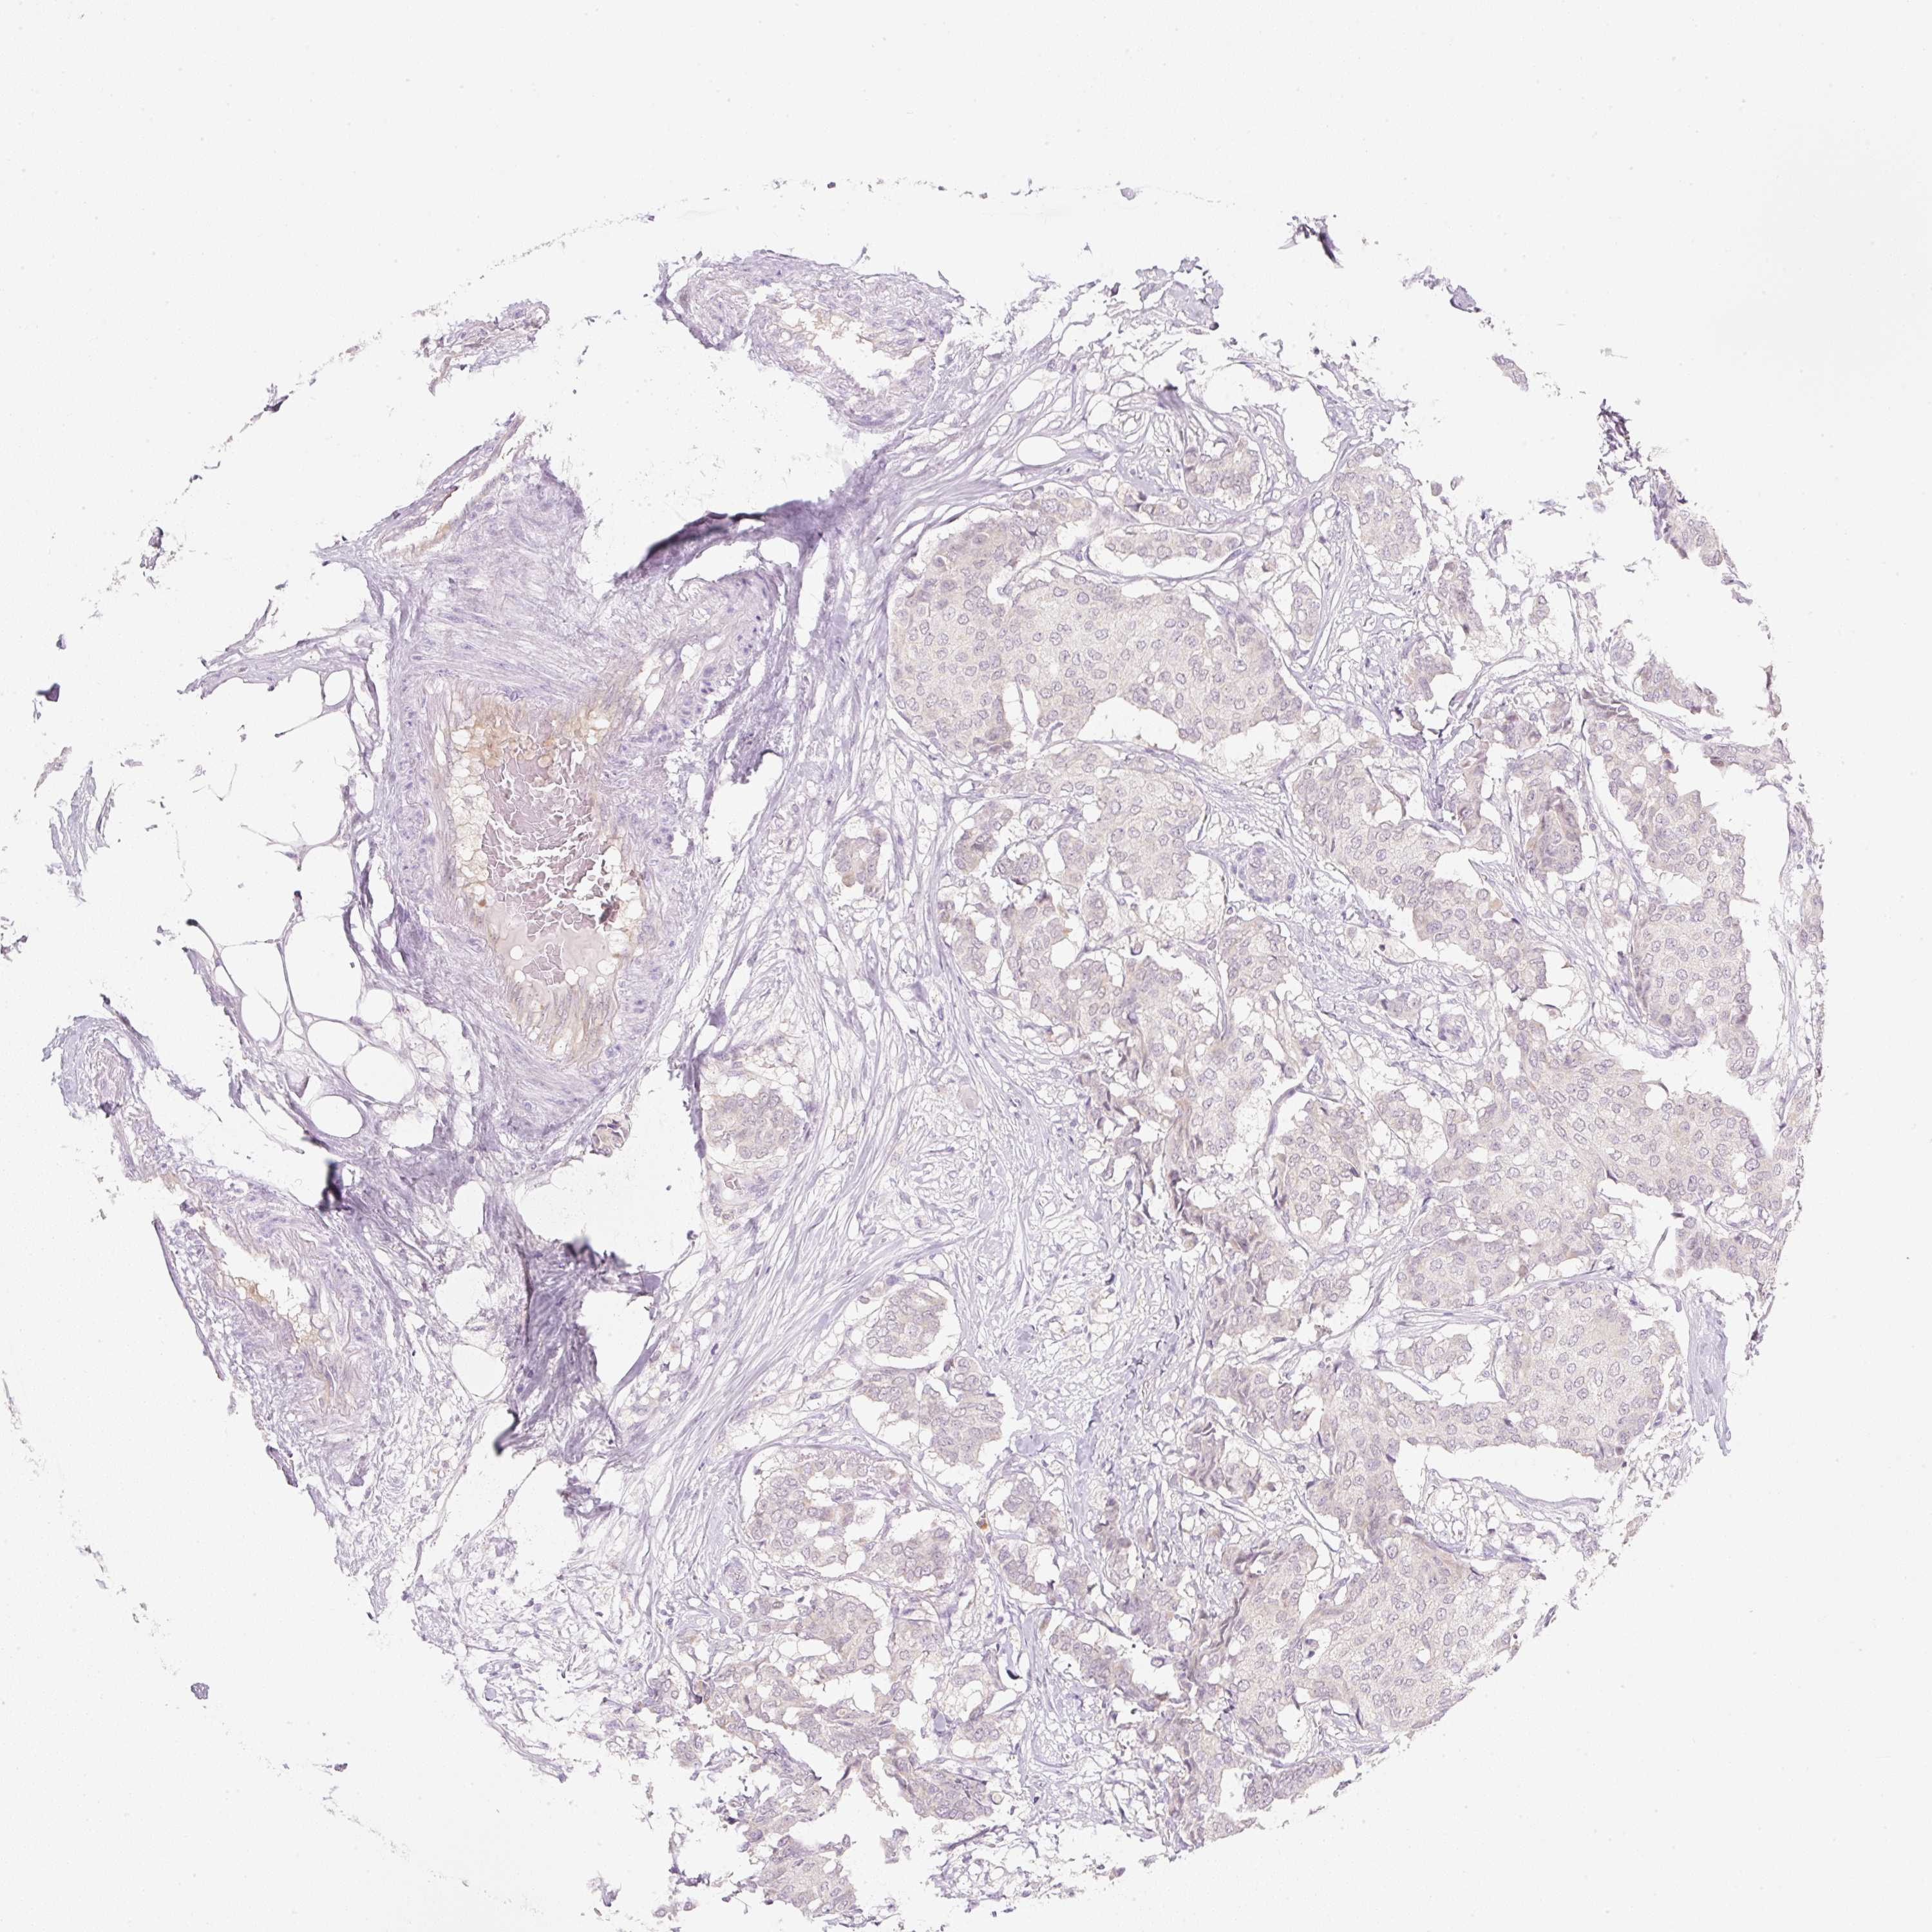

CANCER BREAST CANCER Show tissue menu

BRCA TCGA BRCA VALIDATION PROTEIN EXPRESSION